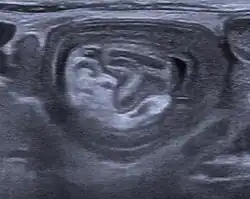

An intussusception is often suspected based on history and physical exam, including observation of Dance's sign. A digital rectal examination is particularly helpful in children, as part of the intussusceptum may be felt by the finger. A definite diagnosis often requires confirmation by diagnostic imaging modalities. Ultrasound is the imaging modality of choice for diagnosis and exclusion of intussusception, due to its high accuracy and lack of radiation. The appearance of target sign (also called "doughnut sign" on a sonograph, usually around 3 cm in diameter, confirms the diagnosis. The image seen on transverse sonography or computed tomography is that of a doughnut shape, created by the hyperechoic central core of bowel and mesentery surrounded by the hypoechoic outer edematous bowel.[10] In longitudinal imaging, intussusception resembles a sandwich.[10] It is also called "pseudokidney" sign because hyperechoic tubular centre is covered by a hypoechoic rim producing a kidney-like appearance.[11]